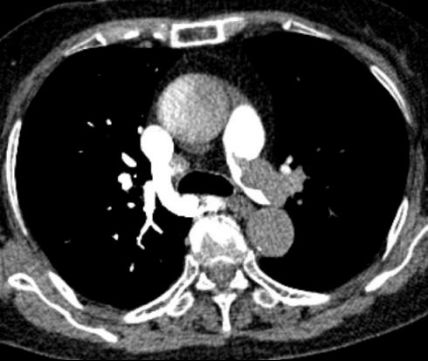

急診醫生快速研判,高度懷疑為急性肺栓塞。肺動脈CTA檢查結果證實了判斷:雙側肺動脈主干及分支存在多處血栓栓塞,右心室明顯擴大——這是急性肺栓塞的典型征象,說明肺動脈堵塞已導致右心室負荷急劇增加,心臟功能受損。

圖:胸部增強CT(CTPA)示右肺動脈主干及分支內可見多發充盈缺損提示肺動脈栓塞